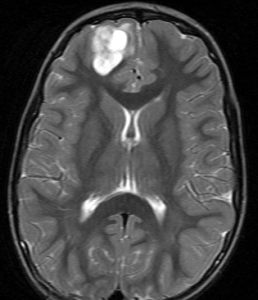

小児にできた右前頭葉の乏突起膠腫グレード2です。右は術後の写真で,手術だけで治りました。

脳幹部グリオーマ

- NF-1では脳幹部にもたくさんの病変がみられます,

- 特に気をつけなければならないのは,徐々に大きくなってくる脳幹部グリオーマ brainstem gliomaです(ここをクリックすると具体例が見れます)

脳幹部グリオーマと間違えそうなもの

3歳の時に,MRIで脳幹部から小脳のグリオーマを疑われて受診しました。橋が腫れて右小脳にもグリオーマのような白い影があります。でもこれは,NF-1のUBOの大きなものです。びまん性正中グリオーマと誤診されて放射線治療を受けてしまった子供もみたことがあります。治療しなくても縮小していくので,何もしないで経過観察します。右側のMRIは13年後のものです。ほとんど消失しています。